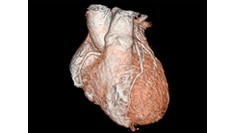

3D Heart

Visualize the anatomical structures and vascularity of the heart with a bright blood, 3D sequence.

Read More

Visualize the anatomical structures and vascularity of the heart with a bright blood, 3D sequence. Read More